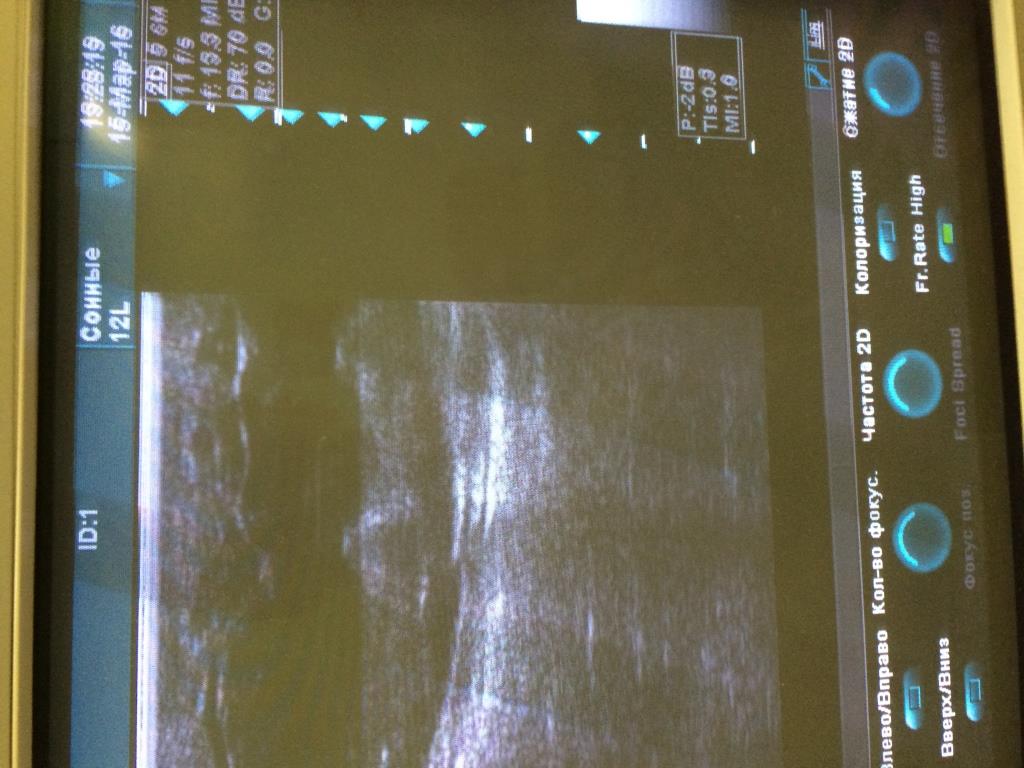

Аппарат Vivid 3 Pro корпорации General Electric Company (производственно-торговый бренд - "GE"), США, 2007 года.

При работе на конвексном и линейном датчике появляется картинка как на фото. Если убираю фокусные зоны либо понижаю частоту дефект пропадает.

Датчики вставлены в разные разъёмы. На конвексном есть небольшой порез акустической линзы, линейный без повреждений.

Предполагаю, что дело не в датчиках.